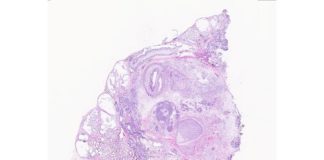

Los teratomas (tumores monstruosos) serían modelo del desarrollo humano

Encontrar el modelo adecuado para estudiar el desarrollo humano, desde la etapa embrionaria temprana en adelante, ha sido un desafío para los científicos durante...